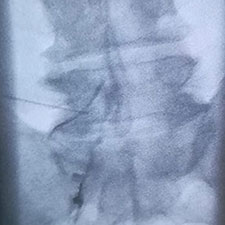

Otra imagen que muestra el contraste dibujando la raíz de L5 izquierda.